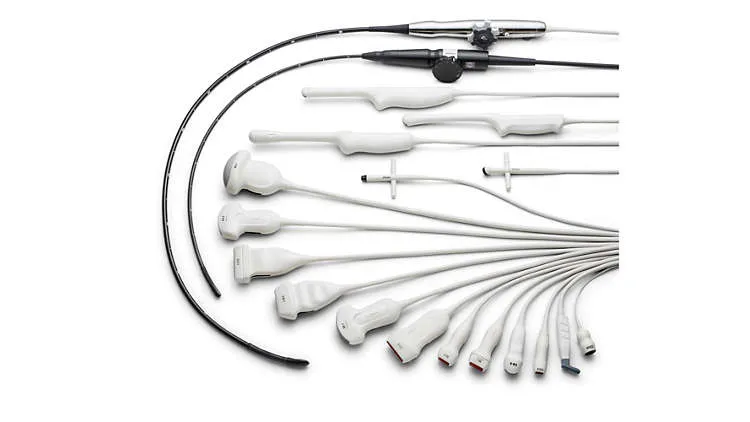

Виды поддерживаемых датчиков

- Конвексный,

- Микроконвексный,

- Карандашный,

- Линейный (до 15 МГц),

- Полостной конвексный,

- Секторный фазированный взрослый,

- Объемный конвексный,

- Интраоперационный линейный,

- Секторный фазированный педиатрический,

- Секторный фазированный неонатальный,

- Чреспищеводный взрослый,

- Линейный высокочастотный (до 18 МГц),

- Объемный полостной, Чреспищеводный педиатрический,

- Объемный линейный,

- Чреспищеводный объемный,

- Объемный кардиологический (трансторакальный)